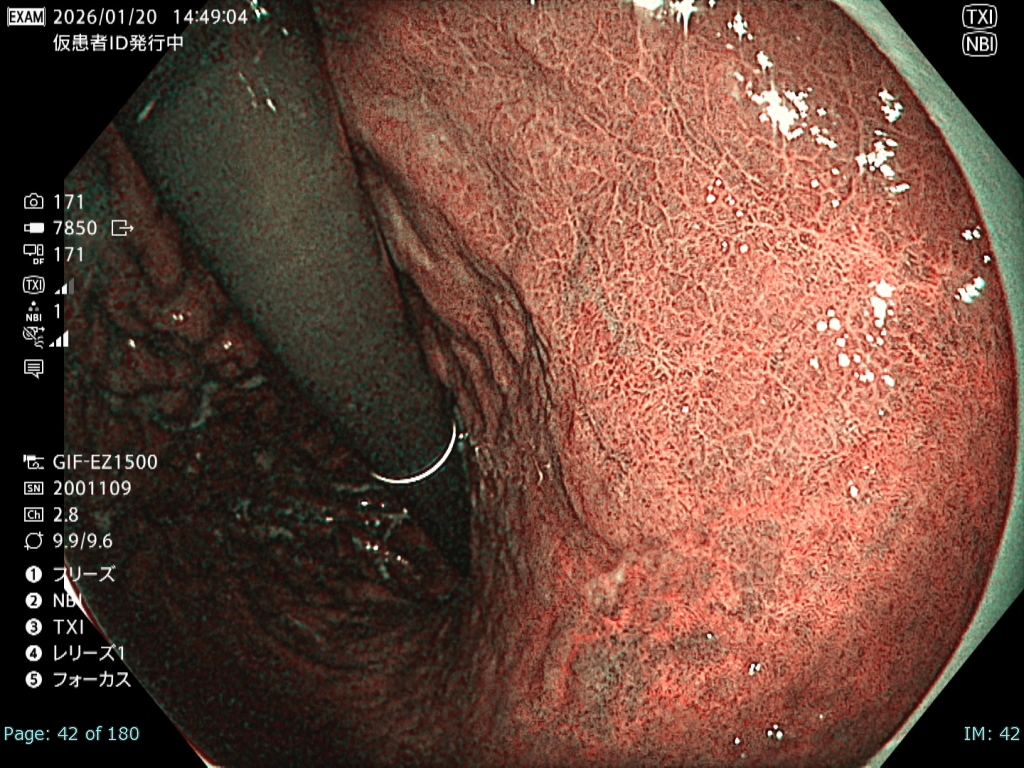

• NBI+TXI観察① (中遠景)

切替前 NBI強調設定:B8

NBI+TXIレベル:中

図4

前述のとおり厳しい状況下でも、NBI+TXI観察モードは、NBI観察と比較して病変をよりシャープに描出出来ると感じた。